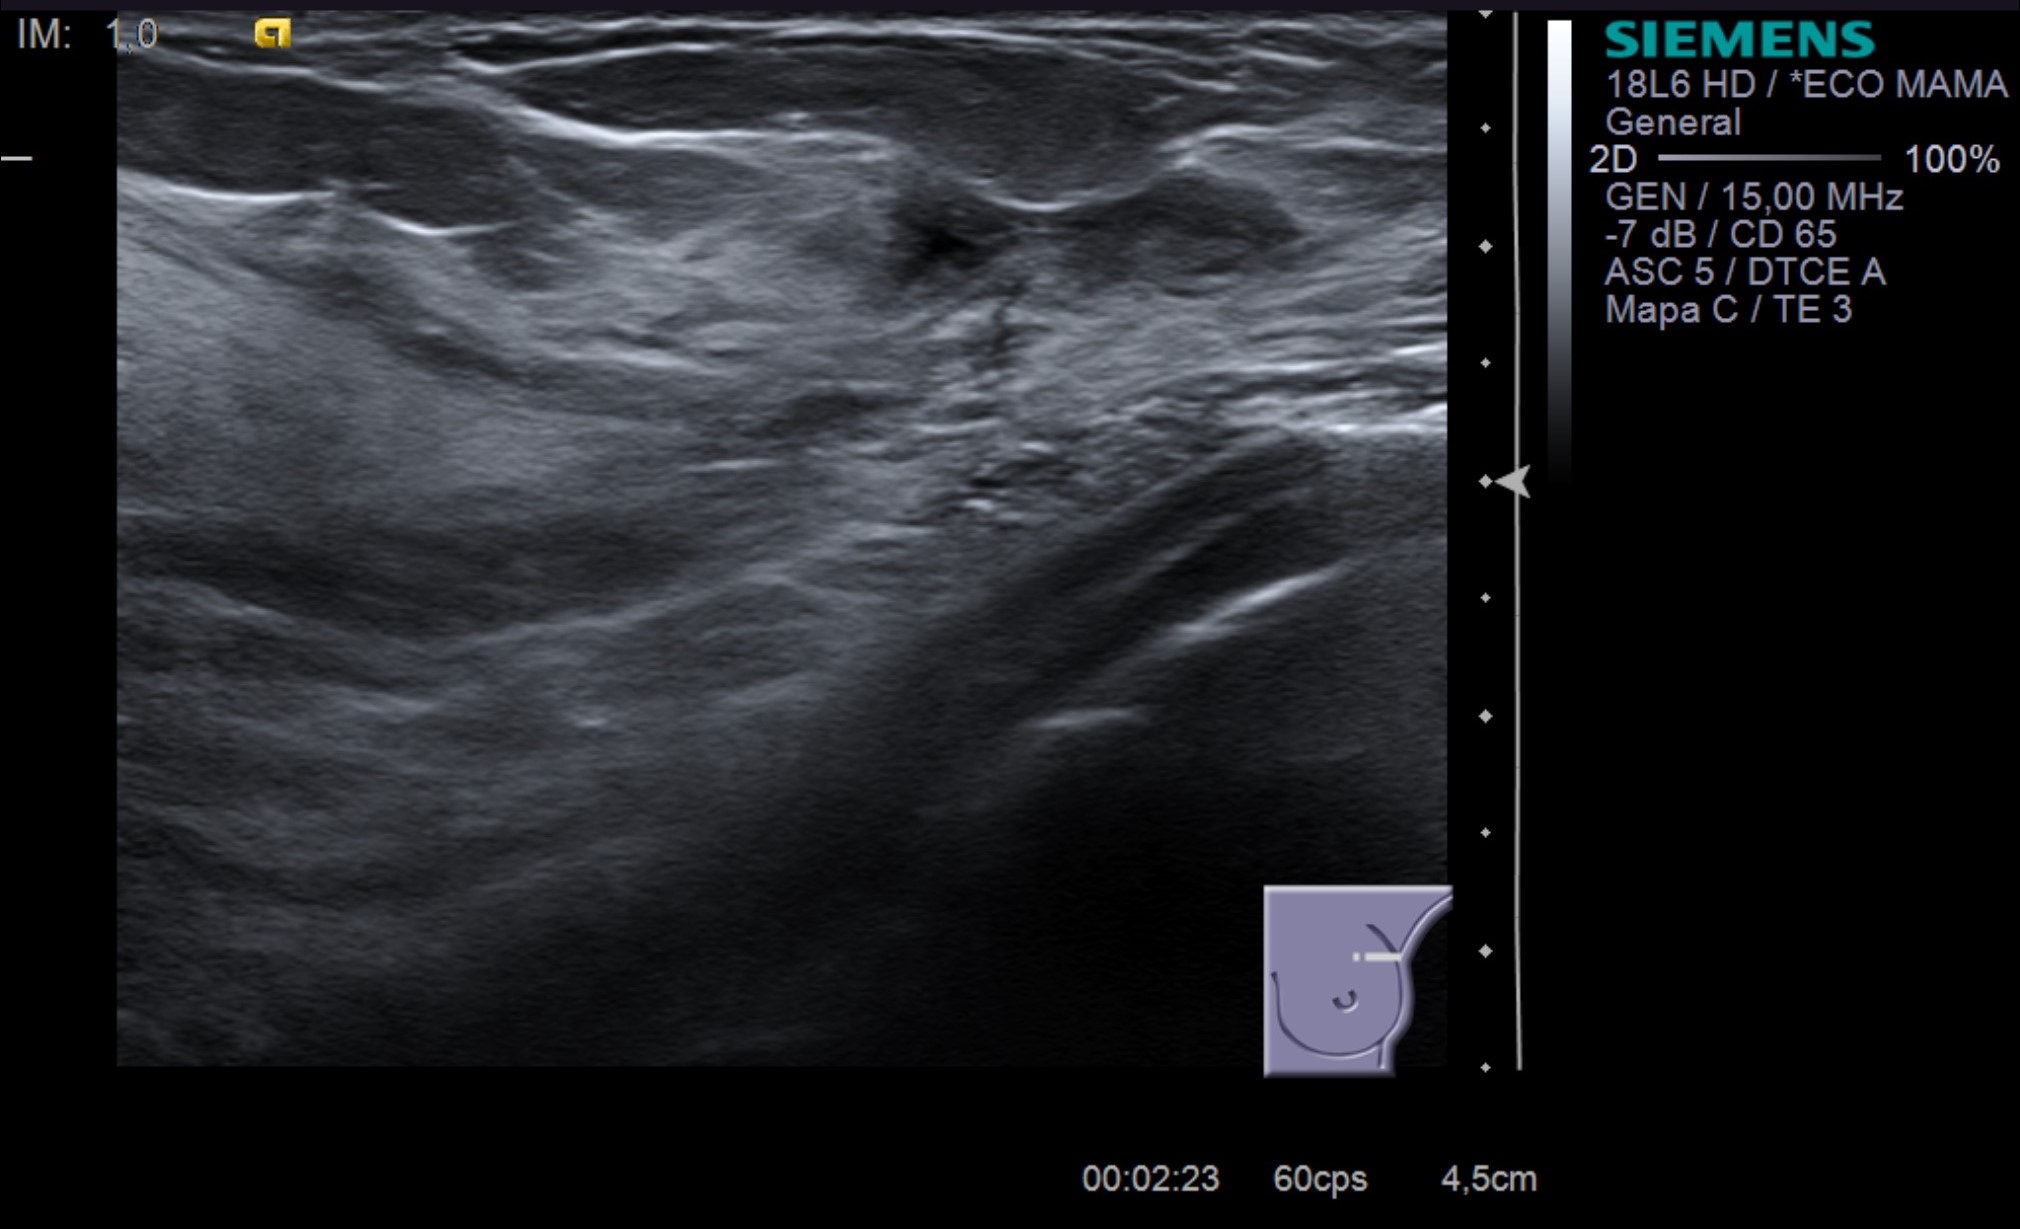

En la ecografía, observamos mamas de ecogenicidad normal para la edad de la paciente. Abundantes quistes bilaterales, vistos en ecografía como nódulos de bordes bien definidos y márgenes circunscritos, anecoicos y con refuerzo acústico posterior. No se identifican nódulos sólidos y los ganglios axilares bilaterales vistos en la mamografía son de características ecográficas benignas. Respecto a la elastografía cualitativa, se visualiza un patrón en grano de café, característico de los quistes.

El quiste de mayor tamaño mide 18 mm de diámetro máximo y se localiza en CSE de mama izquierda. La paciente refiere dolor en relación con dicho quiste por lo que se realiza drenaje PAAF ecoguiado con colapso posterior del mismo y sin complicaciones inmediatas (Imágenes inferiores de PAAF)